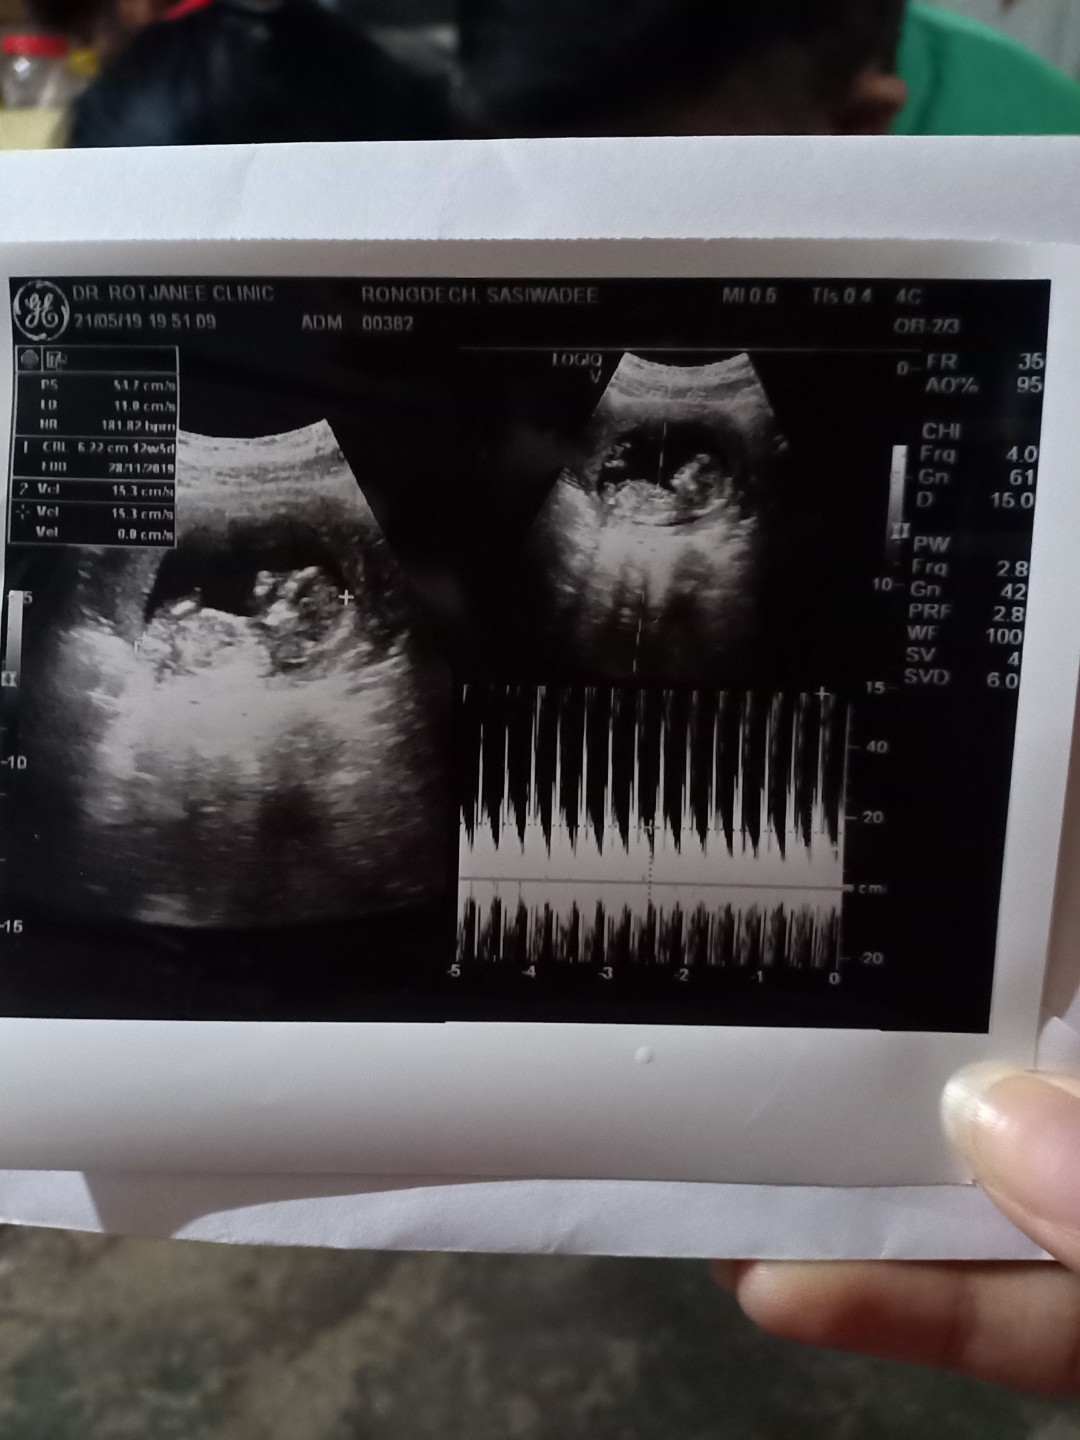

ตอน 8 วีคค่ะ ตอนนี้ 33 วีค 5 วันค่ะ